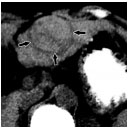

WA术前对比增强CT示肝左叶4.3 cm×5.1 cm肝细胞癌

MWA术后1个月对比增强CT示5.7 cm×6.8 cm凝固灶